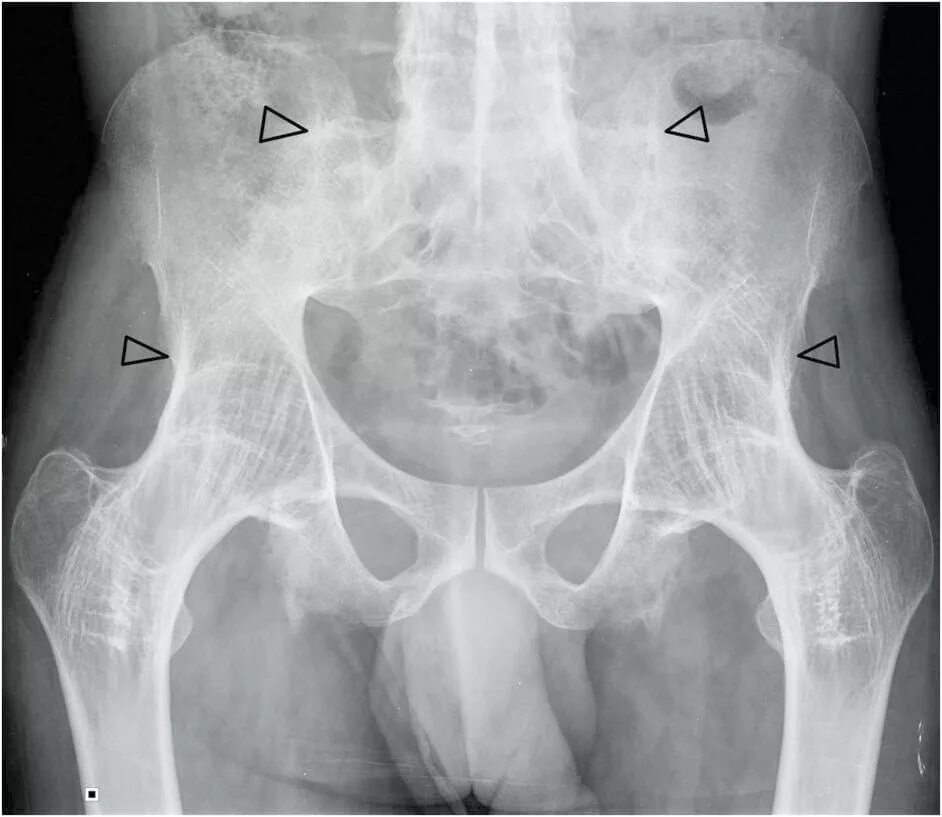

Анкилоз тазобедренного сустава